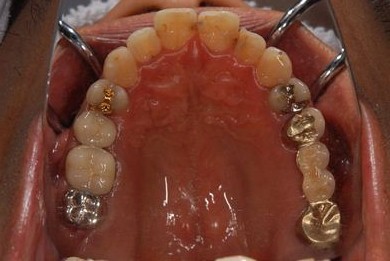

インプラントの症例写真 IMPLANT

インプラント治療+セラミック治療

| 治療内容 | インプラント2本、メタルボンドセラミッククラウン7本(メタルボンド用土台5本)、歯肉歯槽骨整形手術 | ||||||||||||||||||||||||||||||||

| 治療期間 | 11ヶ月 |